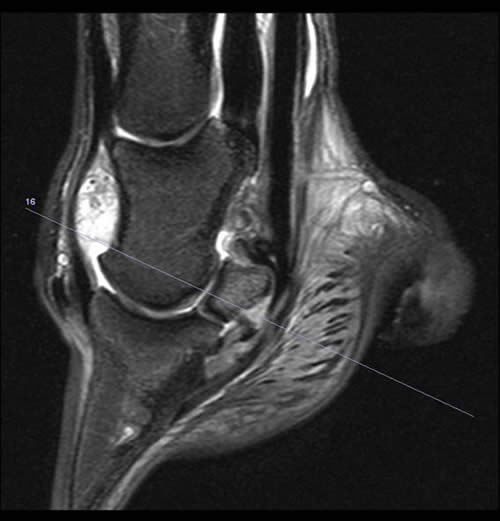

Figure 1: Sagittal 2D STIR sequence showing hyperintense signal at the palmar aspect of the navicular bone and in the DDFT consistent with fibrocartilage loss, cortical demineralisation, focal oedema and fibrosis of the medullary cavity and focal tendonitis of the DDFT (long arrow). In addition the navicular bursal space is obliterated by soft tissue swelling of the impar ligament and adhesion formation between the DDFT and adjacent structures (short arrow).